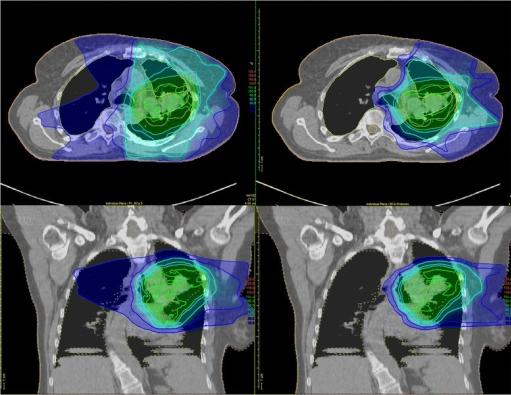

Scans of the chest after traditional radiation therapy and after proton therapy, which show how much surrounding tissue is affected by each type of therapy.

Traditional radiation therapy (top and bottom left) delivers radiation to the tumor and to healthy tissues around the tumor. With proton therapy (top and bottom right), the majority of the radiation is delivered to the tumor.

Credit: Trials. November 2016. doi: 10.1186/s13063-016-1679-4. CC BY 4.0.